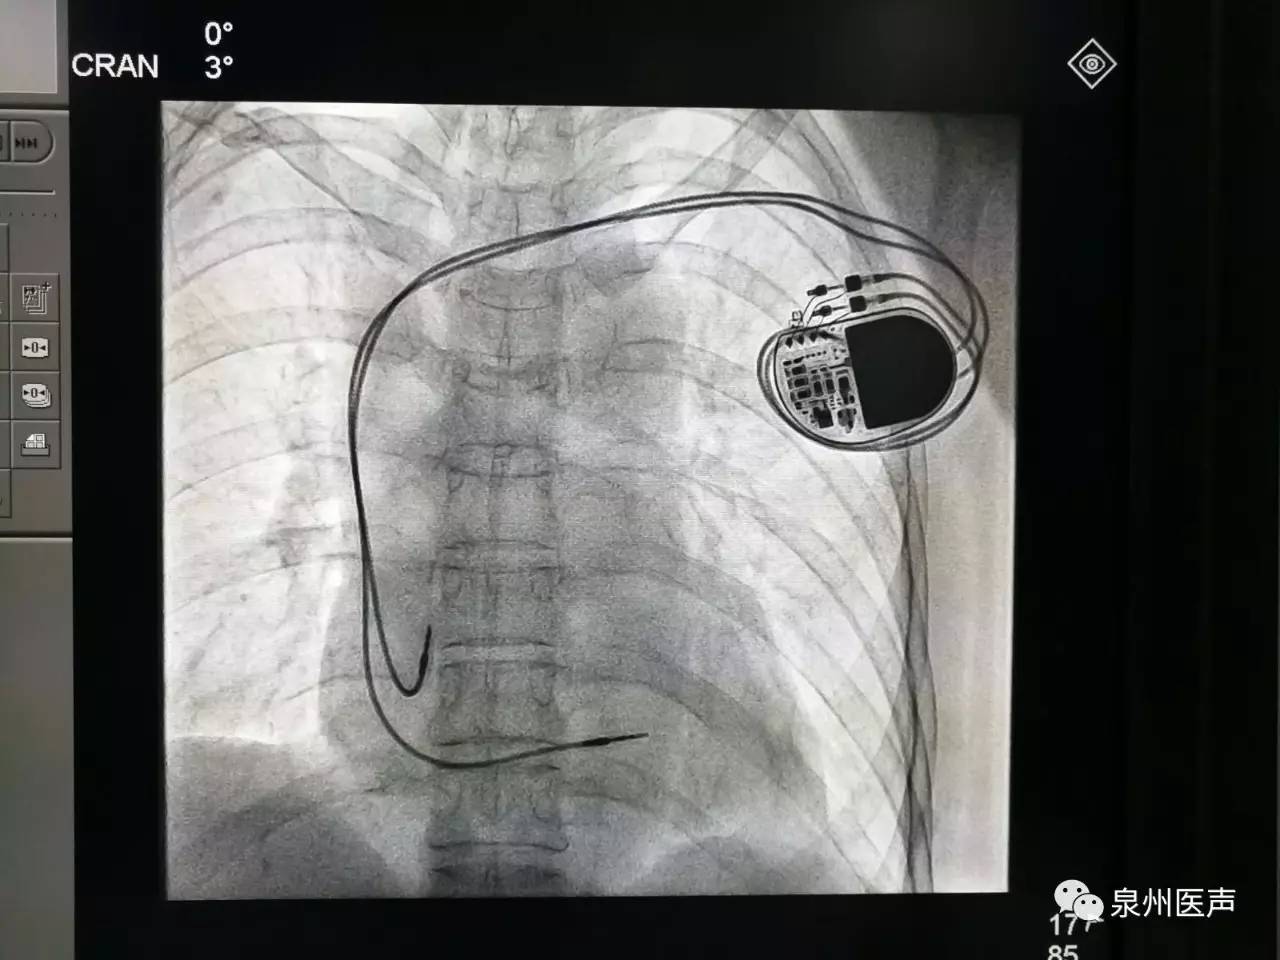

心臟起搏器的日常護理

心臟起搏器出院的宣教,是心內科醫護人員不容忽視的一項工作